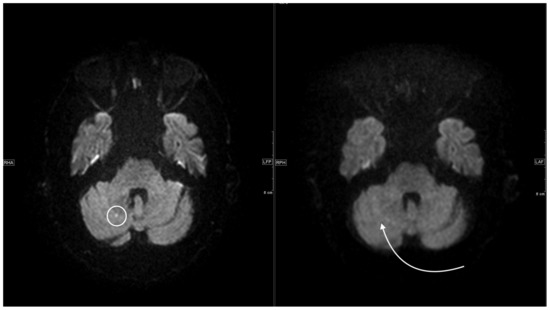

| Patient 5 | 58 | facial droop, hemiparesis right side | 10 | S | multiple subacute infarcts posterior circulation on both sides | 40 | 1050 |